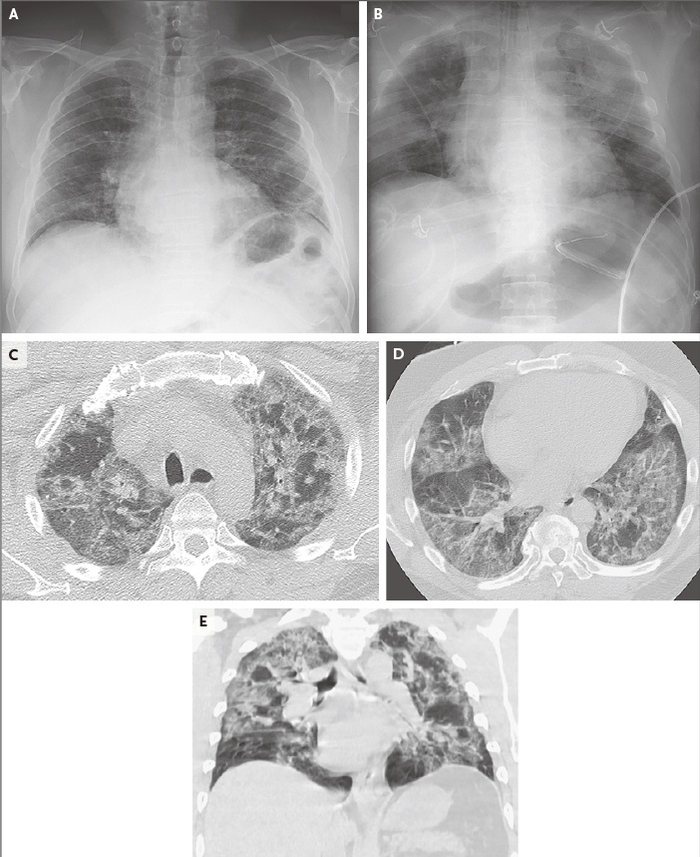

进入ICU时,医院为23例患者(96%)拍了胸部X光片,所有X光片均显示双侧肺部混浊,未见胸腔积液。5例患者(21%)做了胸部CT扫描,其中4份扫描显示双侧毛玻璃状混浊,另1份显示肺结节。

24例危重新冠患者接受ICU治疗的结果,红色表示在ICU接受机械通气

幸存者中,住院天数的中位数为17天,ICU住院中位时间为14天。样本患者中,机械通气的中位时间为10天,截至2020年3月23日,已有6例患者(33%)拔管。